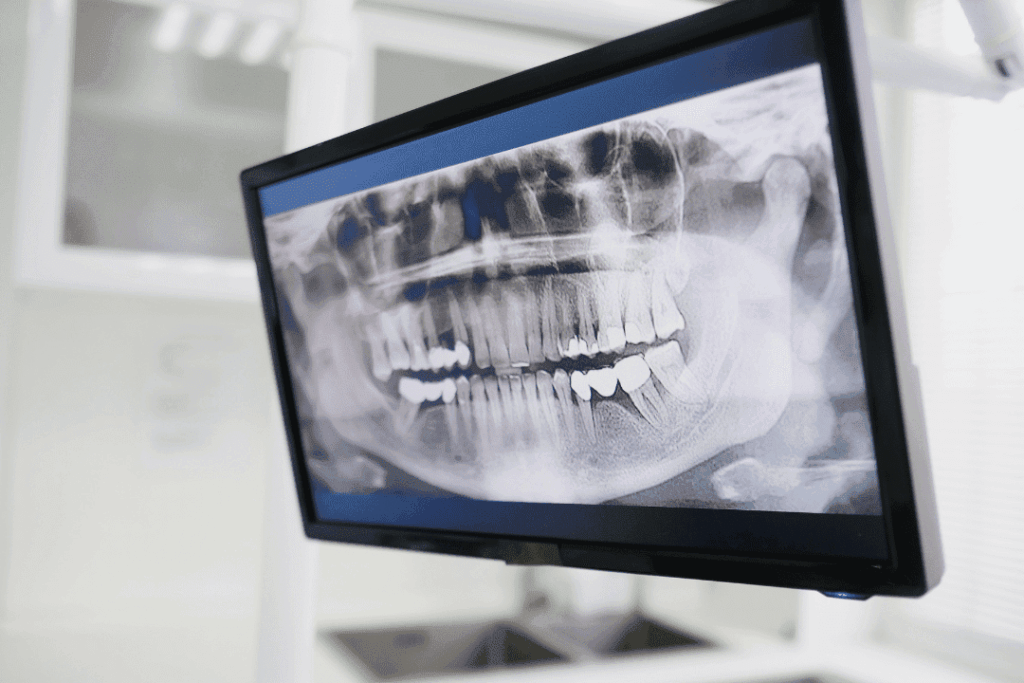

While digital scans capture surface-level details, 3D imaging goes even deeper, offering a full picture of the patient’s bone structure, tooth roots, airway space, and jaw alignment. These tools often cone-beam CT scanners give orthodontists crucial insights into how teeth sit within the jaws and how surrounding structures contribute to alignment issues.

This technology is especially valuable in complex cases, where understanding root position or jaw relationships is essential for safe, effective treatment. With 3D imaging, orthodontists can make decisions that protect long-term oral health, not just aesthetics.

How is 3D imaging different from traditional X-rays?

3D imaging shows tooth roots, jaw joints, airway space, and bone structure in far greater detail than standard X-rays, helping orthodontists diagnose problems more precisely.